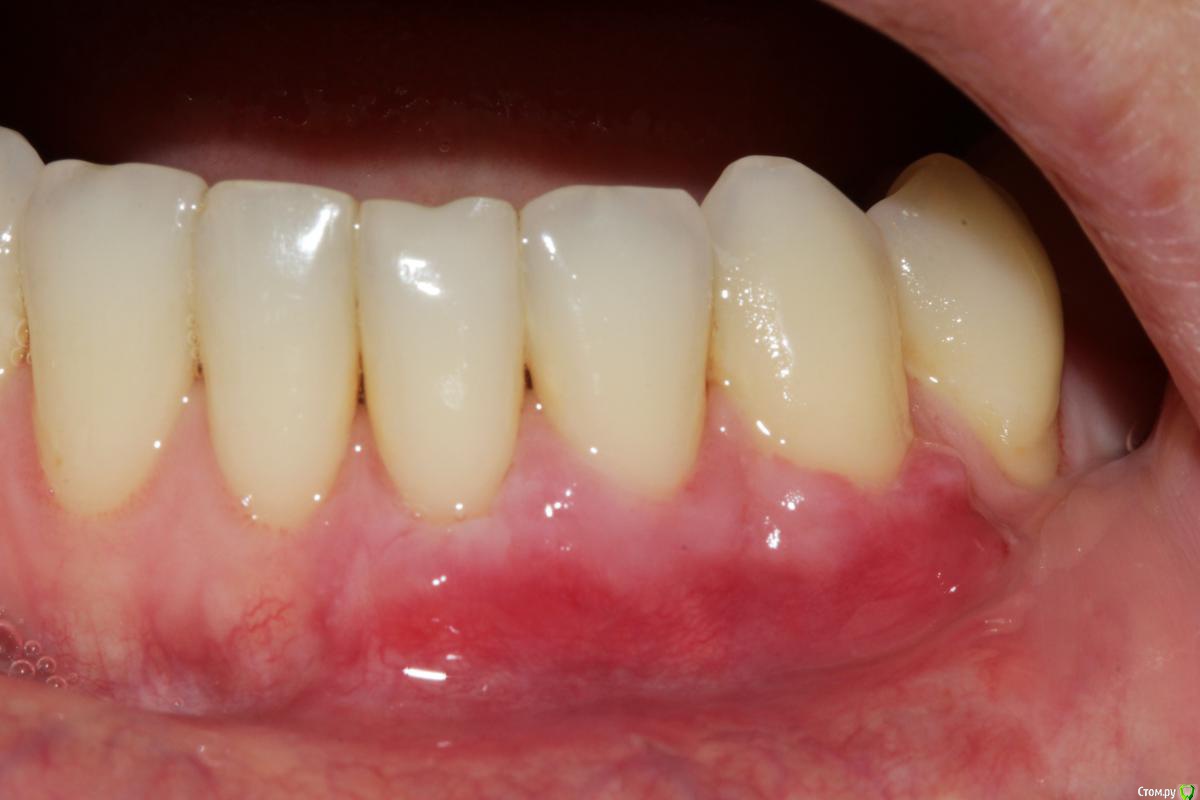

Dc.Petrov Опубликовано 18 сентября, 2015 Поделиться Опубликовано 18 сентября, 2015 Хочу узнать мнение коллег. Можно ли считать результат удовлетворительным? Рассчитывал на лучший итог. 15 Ссылка на комментарий

zzkz Опубликовано 19 сентября, 2015 Поделиться Опубликовано 19 сентября, 2015 через 3-6 мес можно точно сказать, на сегодня все нормуль. 31 еще можно подтянуть. Ссылка на комментарий

zzkz Опубликовано 22 сентября, 2015 Поделиться Опубликовано 22 сентября, 2015 До ЦЭС у 31 и 34 кажется что можно, по крайней мере по фото Ссылка на комментарий